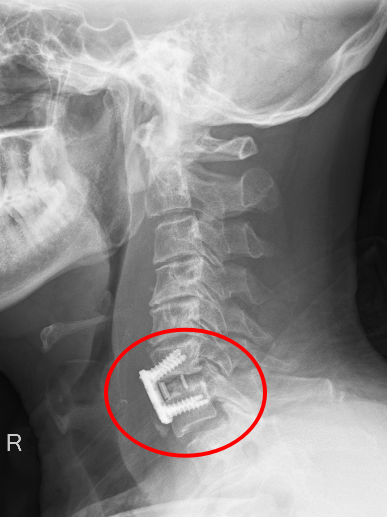

患者朱先生因意外从高处坠落,颈部剧痛、四肢麻木无力,急诊入院后经CT及MRI检查确诊为第6颈椎骨折脱位伴脊髓损,随时可能引发呼吸衰竭或永久性瘫痪。传统保守治疗风险极高,骨科主任彭李华主任医师及脊柱专业组长张利强,迅速组织多学科会诊,结合国际最新指南与患者个体情况,果断制定“前路颈椎间盘切除+植骨融合内固定术”方案,以微创技术最大限度减少神经损伤,脊髓受压明显减轻,重建颈椎稳定性。

术后影像显示,颈椎序列完美复位,内固定位置精准,患者次日即感双上肢麻木缓解,肌力较术前明显改善,术后第二天,患者颈部及双上肢疼痛症状消失,在颈托保护能自主下床行走,术后一周痊愈出院。